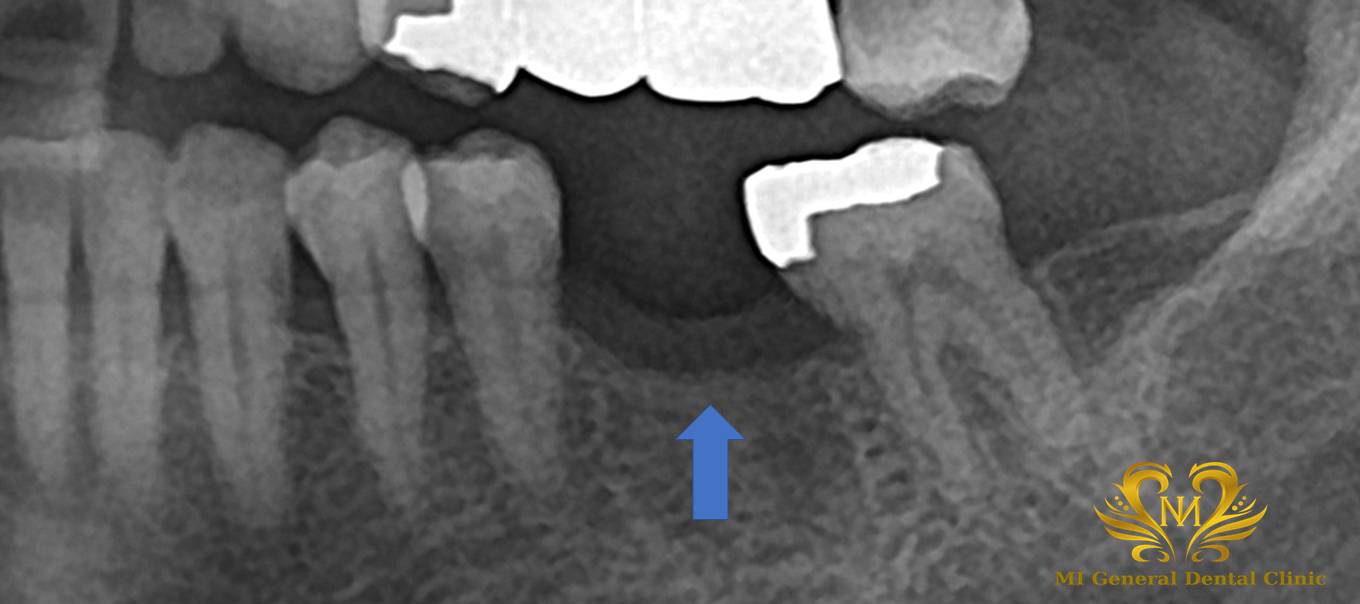

治療前

左下の奥歯に銀歯が入っていた歯が割れてしまい、他院にて抜歯処置を受けた患者様が来院されました。

抜歯後の治療方法について検討される中で、しっかり噛めるようにしたいというご希望があり、インプラント治療を希望され当院を受診されました。

初診時には、現在のお口の状態を詳しく確認するため、レントゲン撮影や口腔内の診査を行いました。検査結果をもとに、後日あらためて院長によるコンサルテーション(治療説明)のお時間を設けています。

コンサルテーションでは、検査結果をもとに現在の状態を説明し、治療の流れや期間についてお話しします。